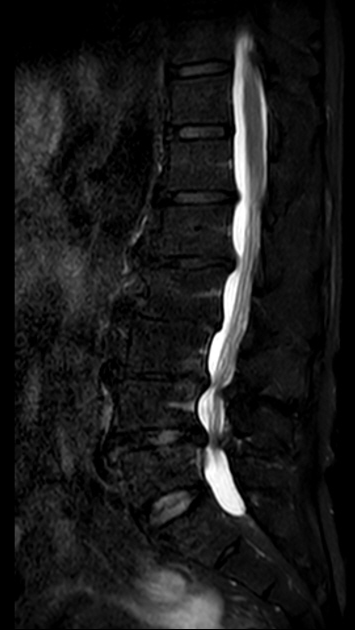

陈勇主任在医学3D打印技术团队的支持下,通过术前采集患者目标椎体的三维信息,运用3D打印技术重建脊柱三维模型,设计椎弓根螺钉的置入钉道,有效控制置钉的位置、方向及角度,从而提高置钉的准确性和成功率,以减少术中置钉过程中神经损伤的风险。

▲3D打印直观显示椎体结构,指导手术精准置钉